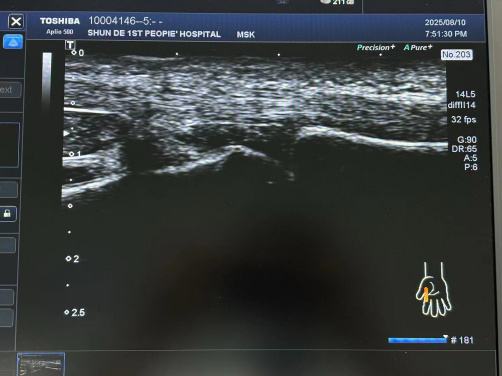

肌骨超聲引導(dǎo)下注射及針刀治療

肌骨超聲作為一種高分辨率的超聲成像技術(shù),具有無創(chuàng)、實(shí)時(shí)、動(dòng)態(tài)及可重復(fù)性高等優(yōu)點(diǎn),在評估關(guān)節(jié)及周圍軟組織病變方面具有獨(dú)特優(yōu)勢。能夠清晰顯示關(guān)節(jié)囊、滑膜、肌腱、韌帶等軟組織的細(xì)微結(jié)構(gòu)。

超聲實(shí)時(shí)引導(dǎo)下,PRP 注射可精準(zhǔn)進(jìn)入病變關(guān)節(jié),其激活后釋放的因子能促軟骨修復(fù)、抑炎止痛、改善功能;玻璃質(zhì)酸鈉注射可補(bǔ)充滑液、緩沖應(yīng)力、抑炎,保護(hù)修復(fù)軟骨。超聲引導(dǎo)下針刀微創(chuàng),可視動(dòng)態(tài),可實(shí)時(shí)調(diào)方案,減時(shí)、降并發(fā)癥、提療效。